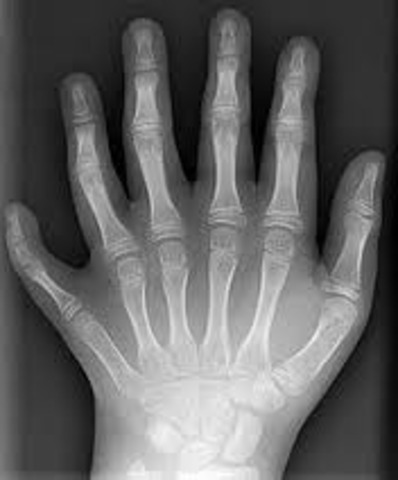

• Raigs X, Roentgen

Raigs X, Roentgen

El terme raigs X o radiació X designa una part de l'espectre electromagnètic que correspon a radiació menys energètica que els raigs gamma, però més que els raigs ultraviolats. La seva longitud d'ona està compresa entre 10 nanòmetres i 100 picòmetres, que correspon a freqüències de 30 PHz a 3 EHz). Foren descoberts pel físic alemany Wilhelm Röntgen.